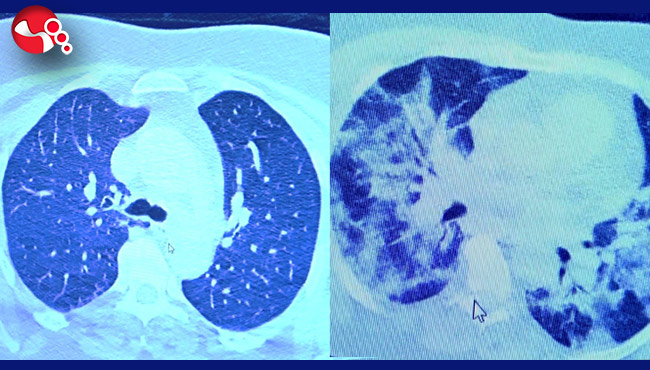

VM Medical Park Samsun Hastanesi’nde görev yapan Göğüs Hastalıkları Kliniği’nden Prof. Dr. Şevket Özkaya da bir hafta ilaç kullanmayan bir pozitif hastanın akciğer tomografisini inceledi. Hasta pozitif haldeyken ilk akciğer tomografisine bakıldı. Tomografide akciğerlerdeki tutulmanın az olduğu gözlemlendi. Akabinde aynı hastanın verilen ilaçları kullanmamış ve 1 hafta boyunca tedaviye uymamış haldeki akciğer tomografisine bakıldı. Sonuç ise ilaç kullanımının önemini ortaya çıkardı. Hastanın akciğer tomografisinde yaygın buzlu camların ve hava yollarının hava yerine ciddi şekilde sıvı ile dolduğu gözlemlendi.

Akciğer tomografisinde oluşan değişim ile ilgili bilgi veren Prof. Dr. Şevket Özkaya, "Ekranda 55 yaşında bir kadın hastamızın filmini görüyorsunuz. Bu kadın hastamız acil servisimize ateş şikâyetiyle geldi ve korona virüsünden şüphe ettik. Testini yaptığımızda ise testin sonucu pozitif geldi. Tomografi çektiğimiz zaman akciğerlerinde henüz ciddi bir tutulum görünmezken hastamız 55 yaşında olduğu için her an ilerleyebilir korkusuyla Sağlık Bakanlığımızın önerdiği ilaçları ve reçeteyi hastanemizden kendisine verdik. Hasta kendini evde karantinaya aldı fakat sonradan öğrendik ki tereddüt ettiği için ilaçlarını kullanmayarak kendini evde tedavisiz bırakmış. Yaklaşık bir hafta sonra aynı hasta acil servisimize bu sefer solunum yetmezliği şikâyetiyle geldi. Solunum yetmezliği gelişince hastanın akciğer tomografisinde ‘buzlu cam’ dediğimiz ve daha ileri konsolide alanların oluştuğunu gördük. Yaygın akciğer harabiyeti dediğimiz bir tablo oluşmuştu. Bu durumda hastada solunum yetmezliği olduğu için yoğun bakıma almak zorunda kaldık" dedi.